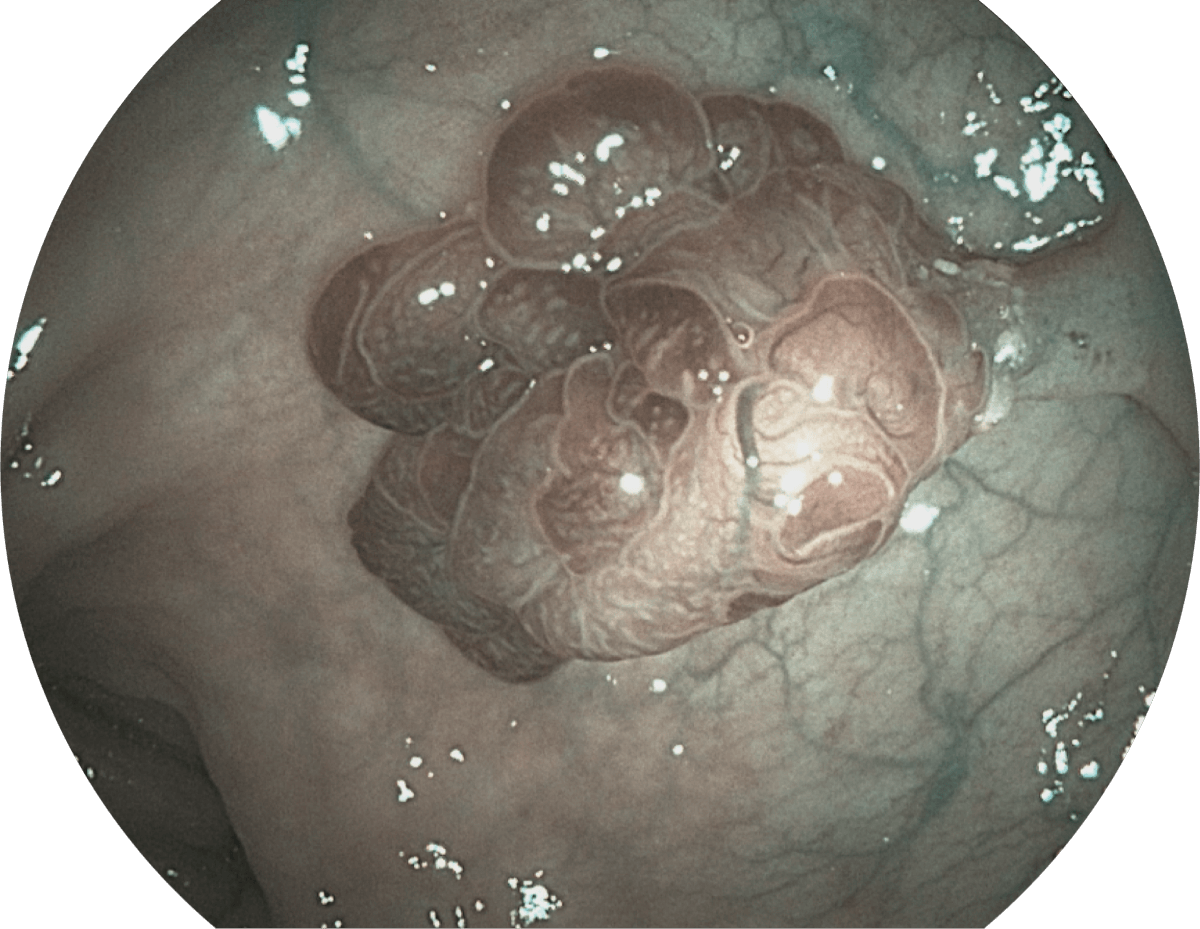

具有聚谱成像技术(SFI)及光电复合染色成像技术(VIST),可完美呈现粘膜细节及病变特征。

WL

SFI

VIST